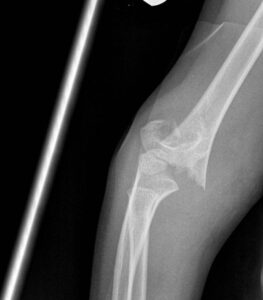

[toggle title=”Baumann açısı (Humerokapitellar açı)” state=”close”]

Lateral kondiler fizeal açı ile humerus uzun ark arasında kalan açıdır.

Normali 10-20°dir. Karşı eklemle karşılaştırılmalı, aralarındaki fark >5° olmamalıdır.

Distal humerus kırıklarının değerlendirilmesi yanı sıra kırıkta yapılan redüksiyon başarısının değerlendirilmesinde de kullanılır.